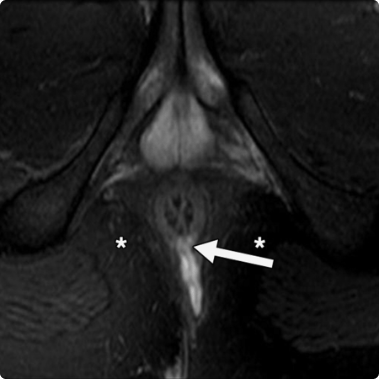

Diagnosis

Your doctor can diagnose anal fistula through a physical exam, medical history and sometimes through imaging tests.

Types of Anal Fistula

- Intersphincteric Anal Fistula: This type of anal fistula is between the internal and external anal sphincter muscles

- Transsphincteric Anal Fistula: This type of anal fistula starts in the anal gland and passes through both anal sphincters to the skin around the anus.